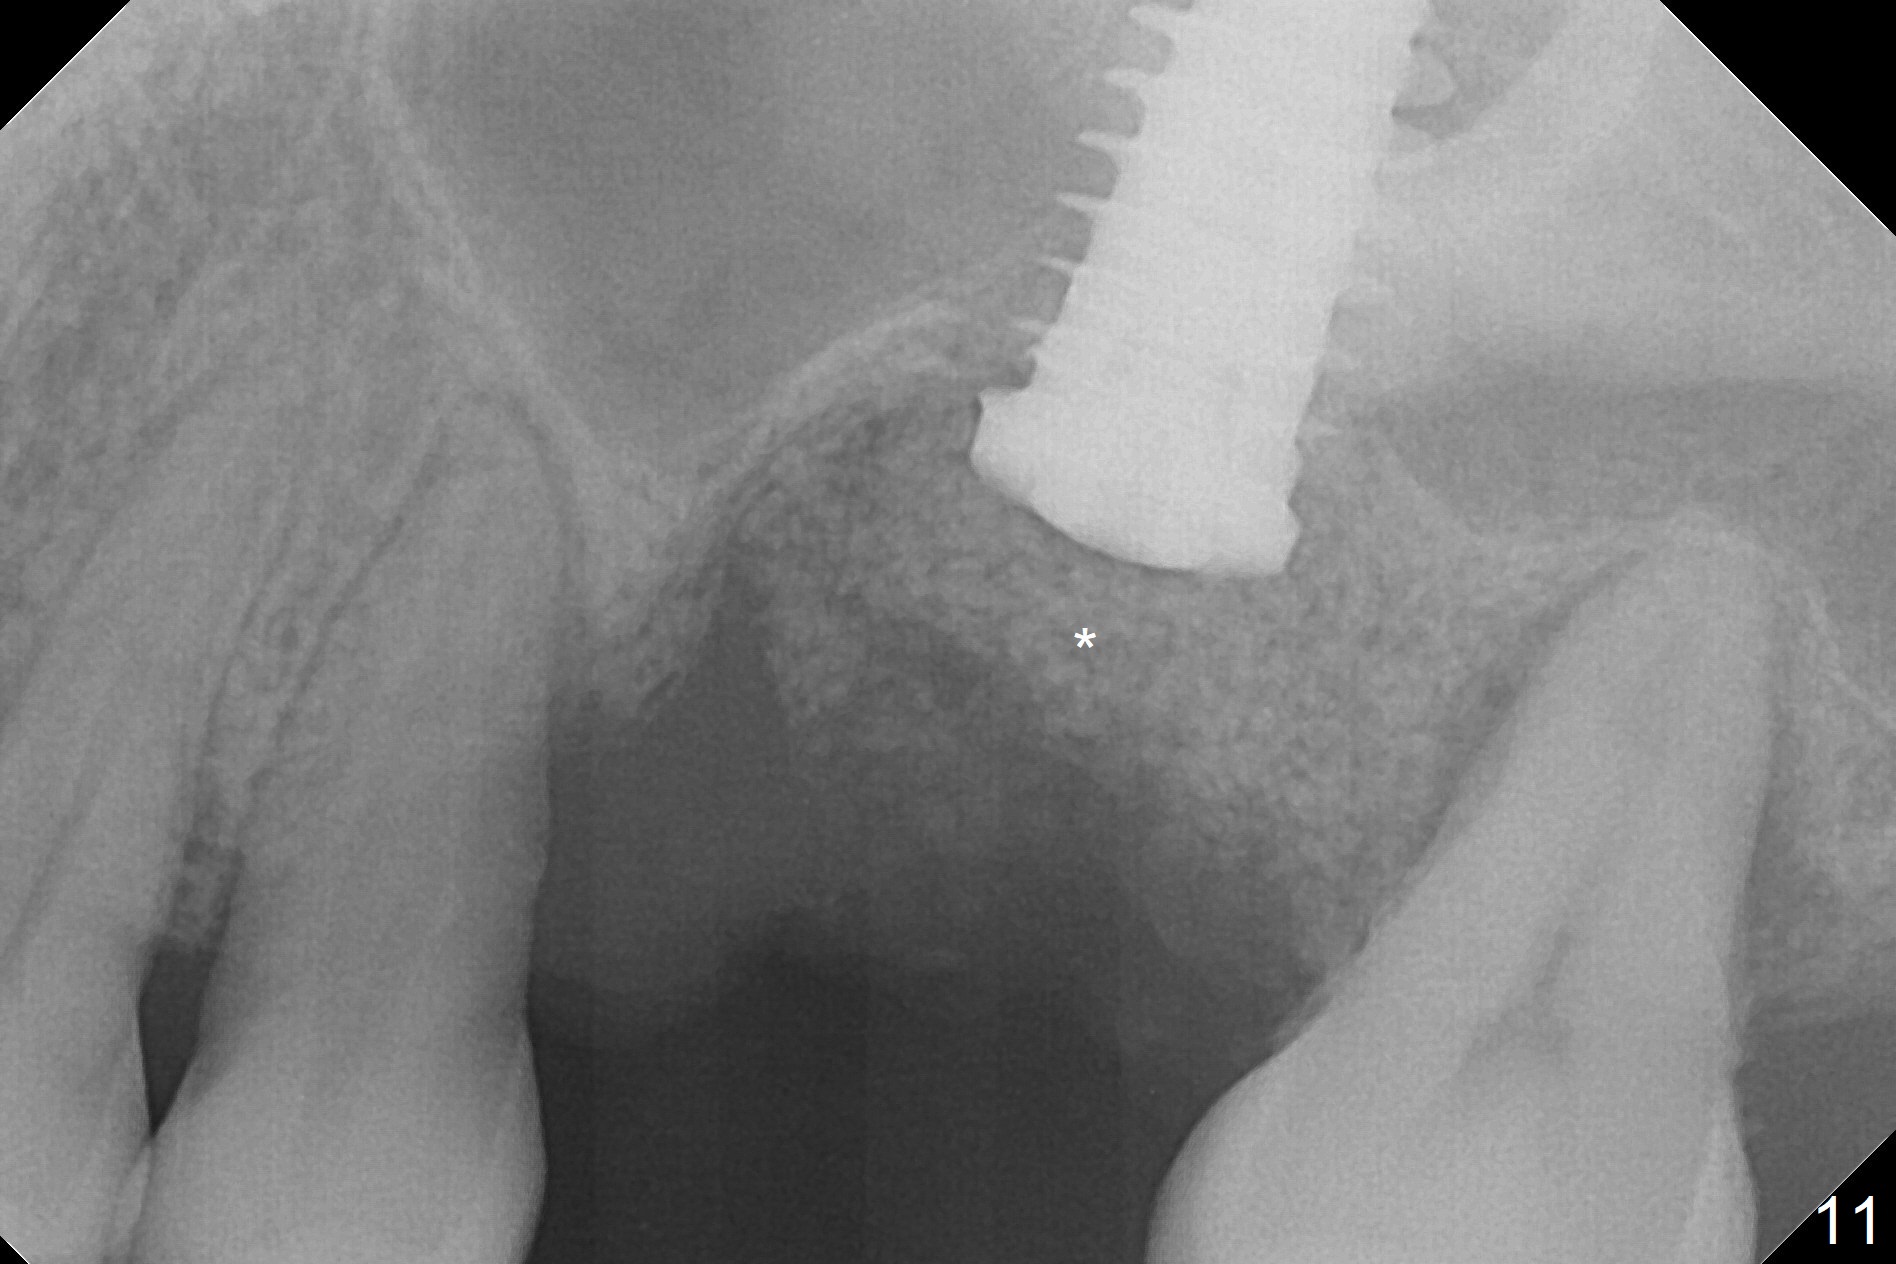

When the displaced tooth #14 (Fig.1) with palatal gingival recession (Fig.2) is extracted, the buccal plate is low, while the palatal one is lost.  Osteotomy is initiated in the bottom of the large socket with Marking Drill.  The bone turns bluish, suggesting thin bone (in fact less than 1 mm as well as low density).  Magic Sinus Lifter (Fig.3 *, Fig.4 blue area) is used for sinus lift (Fig.4 (red curved line: lifted sinus membrane; grey area: a portion of the lifted sinus floor), followed by insertion of a piece of PRF plug and Vanilla bone graft for sinus lift.  The osteotomy is enlarged lightly with 4.8 mm Magic Drill (compare black strips between Fig.4,5).  A 5x9 mm dummy implant (Fig.5 green) is dislodged into the sinus.  The lifted sinus membrane holds the implant in place.  The black thin strip in Fig.5 and black circle in Fig.6a (occlusal view) represents the osteotomy.  After increase in the osteotomy with Lindamann bur (Fig.6b red circle), the implant (Fig.6c green) is retrieved with endodontic forceps (Fig.6c two blue dots (beaks of the forceps); Fig.7,8).  With the enlarged osteotomy (Fig.6d), a 6x9 mm dummy implant is placed deep (Fig.9).  The definitive implant is 6.5x11 mm with insertion torque ~ 15 Ncm (Fig.10).  With placement of a healing screw and further placement of allograft (Fig.11 *), the socket is closed with PRF membrane and collagen plug (Fig.12).

Poor visibility for immediate implant in the molar region is another contributing factor for the dislodgement.  The patient returns for follow up 15 days (Fig.15) and 1 month (Fig.16) postop.  Bone graft seems to be stable around the implant.  The socket heals 4 months postop (Fig.20).  The implant seems to have been osteointegrated (Fig.17,18).  It will be backed up for ~ 3 mm to improve implant/crown ratio (Fig.19, as compared to Fig.14).  If it cannot be done, take impression immediately and make a subgingival provisional before suturing.

In fact, there is no coronal bone for the implant to be backed up.  Therefore, impression is taken after uncover and insertion of a 5.5x5.7(4) mm abutment.

There is a mushroom around the implant nearly 5 months postop/immediately before cementation (Fig.21).  The bone density around the implant is low (Fig.22-24' *).